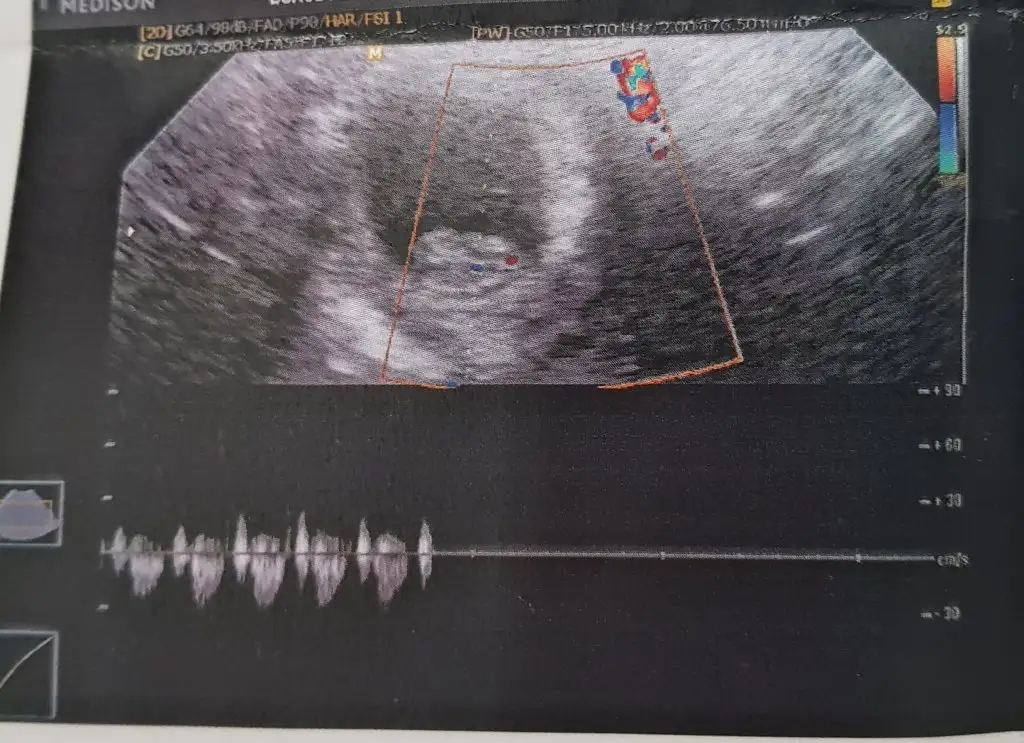

Karından ise erkek nub için 11 yada 12 hafta usg paylaşın10+3 Suan burda 7 haftalik sizce nedir arkadaslar? Bu arada cok tatli telaslar hepimiz icin Allah sagsaglim kucagimiza almayi nasip etsin insallah

Buna göre erkek karından bakıldıysa nub için 11 yada 12 hafta paylaşınBanada tahmin yaparmisiniz 8 haftalik

Teşekkürler canım karındandi evetKarından ise erkek nub için 11 yada 12 hafta usg paylaşın